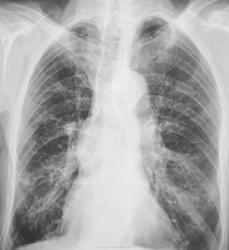

Зацепили по "флюшке"...

Через год.

Еще через год.

И, еще через год.

История "жизни". Спасибо за показательный случай.

А где же первичный очаг?

Первичный очаг чего?

Мелькнула мысль о метастазах...погорячился ...

У нас с коллегой фтизиатром тоже такая мысль мелькнула.